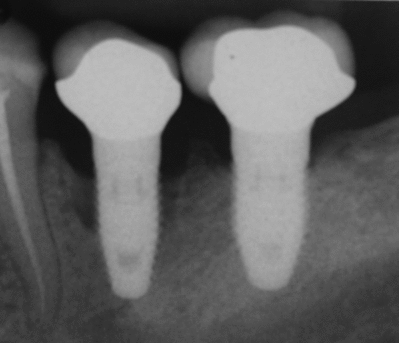

- с помощью рентгенографии изучаются качество и плотность костной ткани;

Под термином «имплантация зубов» в стоматологии понимают только вживление зубного имплантата. В дальнейшем на вживлённый имплантат с помощью цемента крепится коронка, которая может быть временной — пластмассовой, металлокерамической, керамической, золотой и т. д. Относительно кости она должна располагаться на том же уровне, на котором ранее располагалась коронка зуба, замещаемого имплантатом. В практике чаще всего применяются два вида фиксации коронок на имплантаты: цементная или винтовая.